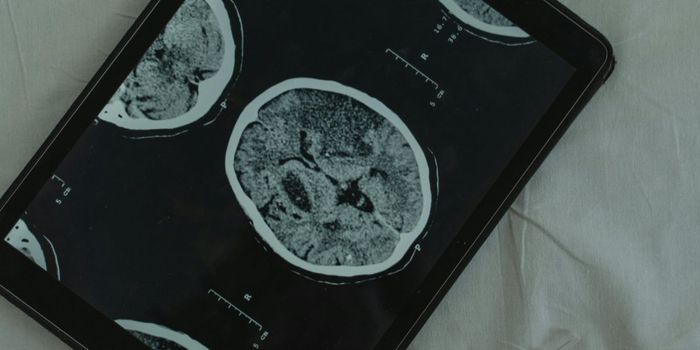

FEB 09, 2025CancerGlioblastoma (GBM), an aggressive form of cancer that grows in the brain or spinal cord, occurs at an incidence rate of ...